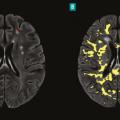

La sclérose en plaques (SEP) est une maladie neuro-inflammatoire chronique du système nerveux central (SNC). Elle est caractérisée par la présence de lésions (ou plaques) au niveau du cerveau et/ou de la moelle épinière et/ou des nerfs optiques. Au sein de ces lésions inflammatoires, la gaine de myéline entourant les axones des…

En dépit de mécanismes auto-immuns incontestés impliqués dans la physiopathologie de la maladie, la sclérose en plaques est de plus en plus considérée comme une pathologie neurodégénérative. Sur le plan clinique, la composante auto-immune se traduit par la survenue de poussées. Sur le plan paraclinique, il s’agit de l’apparition de…